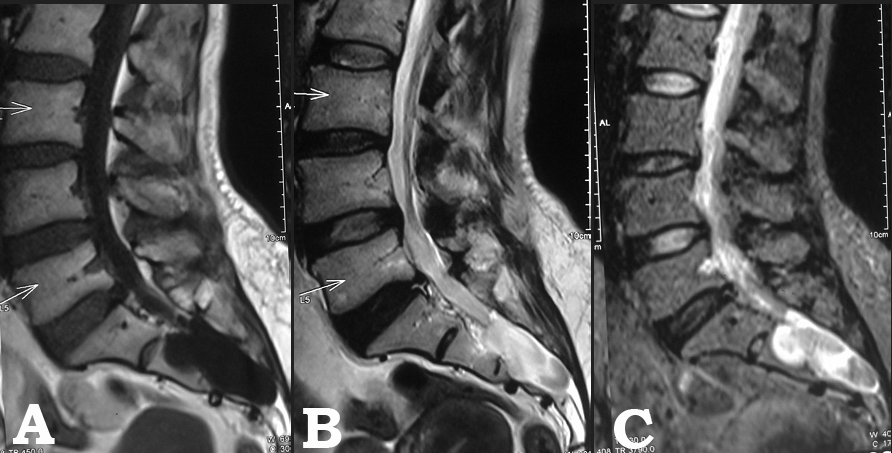

Sacral arachnoid cyst presenting as chronic low back pain

perineural cyst, sacral Tarlov cyst, spinal arachnoid cyst, arachnoid cystAbstract

Bangladesh Journal of Medical Science Vol.14(1) 2015 p.106-108